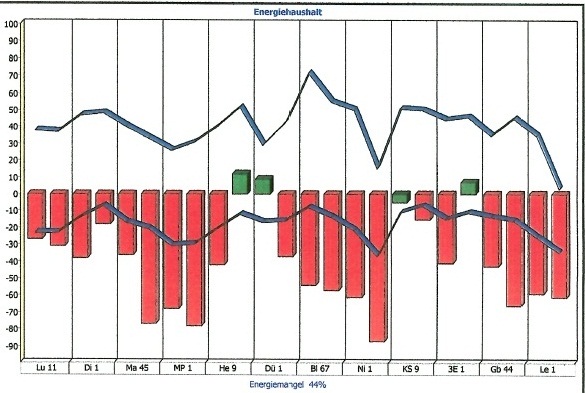

Nachfolgend Ergebnisse einer Studie, die über die Messung des menschlichen Meridiansystems aus der Traditionellen Chinesischen Medizin durchgeführt wurde, vor und nach der Betrachtung von Elementarkunst.

Steigt Energie,

entsteht Kreativität.

Sinkt Energie,

entsteht Arbeit.

Sie können unter Fakten, Ergebnisse aus meiner Studie über die Wirkung der Initiativbilder einsehen, unter "Indirekt" Person 1 und 2 vorher und nachher.